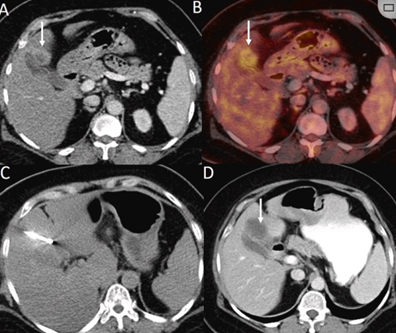

79 岁男性,肝转移(结直肠癌)肿瘤的完全消融病例

( a ) 轴向 MRI 和 ( b ) 轴向 CT 显示肝S8段有一个16mm的病灶,邻近肝缘。( c )冷冻消融期间CT显示放置了2个冷冻探针,低密度冰球包围病灶。(d)术后1个月随访 CT显示冰球对应的坏死区域,未见复发。(f)与基线影像(g)相比,12个月后的FDG-PET/CT显示未见FDG摄取。

(a)轴向CT显示病变位置毗邻心脏和上腔静脉(黑色箭头)。1个月后的轴向(e)和冠状位(f)增强CT扫描显示低密度区域,由于肉芽组织反应引起的边缘增强。

技术成功100%,92% 的病灶中观察到肿瘤完全消融。16 名患者 (33%) 出现局部复发。10 名患者 (20%) 因局部复发或肿瘤消融不完全而接受二次冷冻消融术。

7名患者出现轻微并发症,未发现脓肿形成、胆漏、胆汁瘤或血液学变化。冷冻消融可安全、有效治疗毗邻重要脏器的原发性肝脏肿瘤和肝转移瘤患者,有效控制肿瘤局部进展,使患者生存获益。我国作为肝癌大国,对于肝癌的治疗一直给予高度重视。基于专家共识和相关文献研究结果显示,冷冻消融技术具有高效、低成本、创伤小、适应证广、并发症相对较少等优点,可有效延长患者生存期、提高生活质量、降低患者经济负担。因此,冷冻消融技术在肝癌的应用中有着极高的潜力和广泛的发展空间。